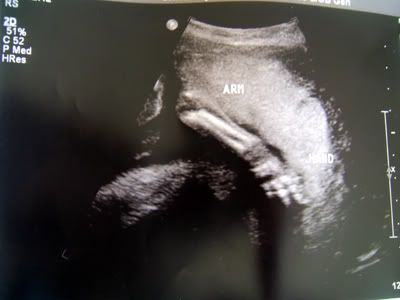

Well, as you all probably know, we're expecting an addition to our little family; a baby boy due Easter weekend this April.  We're excited!  So far, everything looks good and I'm feeling good now that the morning sickness has passed :)  Here a few u/s photos from the 20 week scan......

Arm and placenta in front of his face